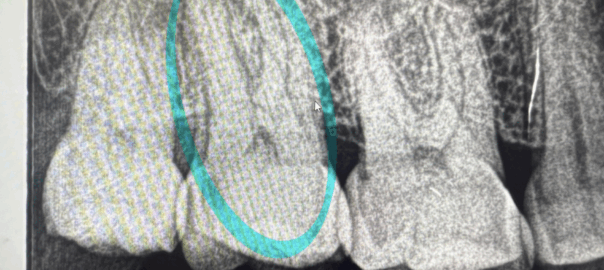

- 2025年9月13日 根っこの再治療

こんにちは、静岡市清水区川原町のわたなべミント歯科です。 今回は、歯の根っこの先に膿がたまったりして、病巣ができてしまった時に行う、感染根管処置という治療についてお話ししたいと思います。 主に神経を取った歯に起こりやすい … 続きを読む 根っこの再治療